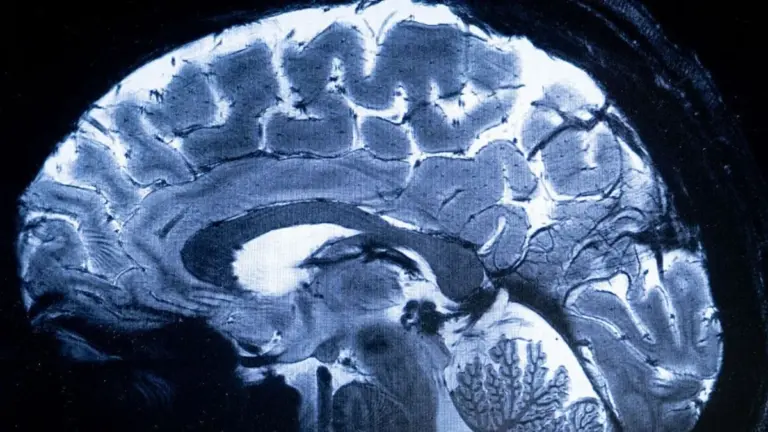

Dlouho jsme tušili, že naše nálada a zdraví mozku úzce souvisí s tím, co se děje v našem břiše. Ale nová studie ukazuje něco mnohem více fascinujícího – a pro někoho možná i trochu děsivého. Živé bakterie mohou fyzicky cestovat z vašeho trávicího traktu až do mozkové tkáně.

V tomto výzkumu na myších vědci z Emory University odhalili, že stačí malá nerovnováha v těle a „bariéra“, která má mozek chránit, se stává průchozí cestou pro mikroskopické vetřelce.

V naší kultuře, kde si rádi dopřejeme těžší jídla, uzeniny a pivo, je zdraví střevního mikrobiomu klíčovým tématem. Často řešíme pálení žáhy nebo nadýmání jen jako estetický problém. Ale tato studie naznačuje, že „propustné střevo“ může být prvním krokem k neurodegenerativním změnám, které se projeví až za desítky let.

Dobrou zprávou je, že tento proces není nevratný. Jakmile se testované myši vrátily ke zdravé stravě, hladina bakterií v mozku klesla pod detekovatelnou mez. To je pro nás obrovská naděje.